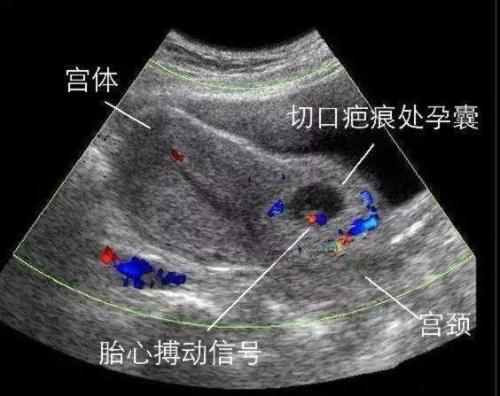

剖宫产术后子宫瘢痕妊娠(cesarean scar pregnancy, CSP)是指受精卵着床于前次剖宫产子宫切口瘢痕处的1种异位妊娠,是1个限时定义,仅限于早孕期(≤12周);孕12周以后的中孕期CSP则诊断为“宫内中孕,剖宫产术后子宫瘢痕妊娠,胎盘植入”,如并发有胎盘前置,则诊断为“宫内中孕,剖宫产术后子宫瘢痕妊娠,胎盘植入,胎盘前置状态”,到了中晚孕期则为胎盘植入及前置胎盘,即形成所谓的凶险性前置胎盘(pernicious placenta previa)。

由于CSP可以造成清宫手术中及术后难以控制的大出血、子宫破裂、周围器官损伤,甚至切除子宫等,严重威胁妇女的生殖健康甚至生命,已引起临床上的高度重视。